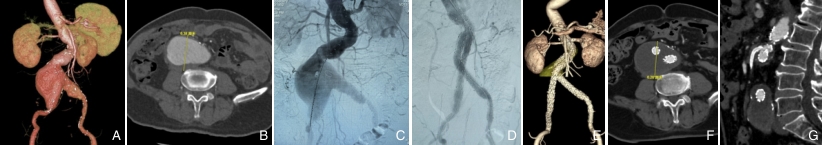

图4 接受IMA重建的患者 A:干预术前,双侧髂内动脉闭塞;B:瘤体最大直径约63.8 mm;C:术中造影证实瘤体,双侧髂内动脉闭塞,且IMA发自瘤体;D:考虑双侧髂内闭塞,若栓塞IMA,有肠道或盆腔内脏器缺血风险,遂行EVAR+IMA重建;E-G:术后1年随访CTA提示,瘤体直径稳定,无明显内漏,IMA直径通畅,患者无肠道及盆腔缺血表现Fig.4 IMA reconstruction in a patient with abdominal aortic aneurysm A: Preoperative imaging showing bilateral internal iliac artery occlusion; B: Maximum aneurysmal diameter of approximately 63.8 mm; C: Intraoperative angiography confirming aneurysm and IMA originating from the sac; D: EVAR combined with IMA reconstruction to avoid intestinal or pelvic ischemia; E-G: CTA at 1-year follow-up showing stable aneurysmal diameter, patent IMA, and absence of endoleak